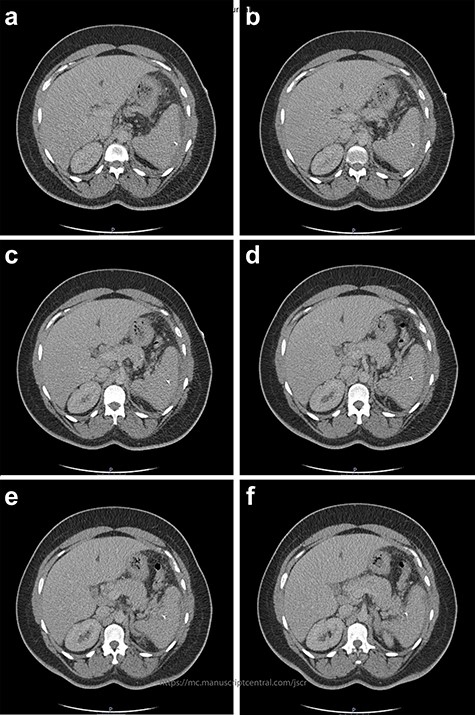

Contact with the previous hospital that treated the patient for her empyema revealed the splenic foreign body pre-dated any hospital admission or intervention; the empyema fluid culture had grown Staphylococcus aureus and S. anginosus, and that there was no splenic collection on CT before the VATS procedure (Fig. 4). The patient had no previous hospital admissions, operations or other exposure to needles; the GP confirmed that there was no past psychiatric history. The patient had moved to the UK from Grenada, Caribbean aged 7 and that she was not aware of any procedures prior to this age.

Two-mm axial sections from a CT scan in January 2020, performed after the VATS procedure, to check resolution of the empyema that shows the foreign body impacted in the spleen without evidence of haematoma. (a) section number 18, (b) section number 19, (c) section number 20, (d) section number 21.